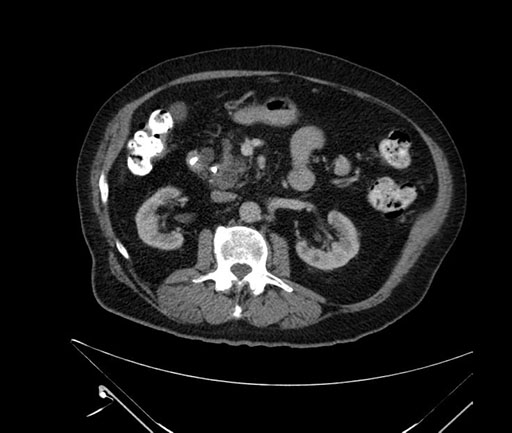

Whipple (pancreaticoduodenectomy) [case 7]

Axial - stented

Imaging analysis

Based on your CT findings, which issue(s) would give reason for "planned slowing down moment(s)" in this case?

Considering a standard Whipple procedure, what step(s) of the operation would you do differently in this case?